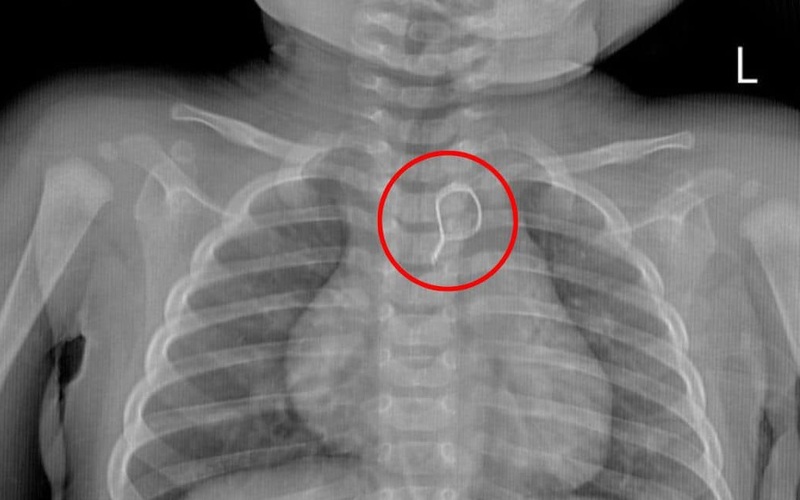

Bệnh nhi nhập viện trong tình trạng quấy khóc nhiều, tự thở đều, da niêm mạc hồng, nhịp tim rõ. Kết quả chụp X-quang cho thấy có dị vật hình tròn cản quang chồng hình trong trung thất.

Ca nội soi gắp dị vật được ThS.BS Nguyễn Quang Huy – Phó Trưởng khoa Nội tiêu hóa trực tiếp thực hiện đã diễn ra thành công. Dị vật được gắp ra là nhung bọc dây kẽm uốn tròn có 1 đầu nhọn với đường kính khoảng 1,5cm.